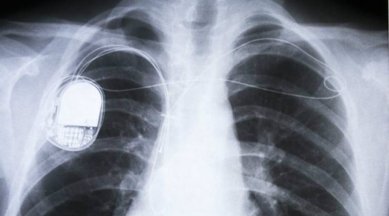

Millions of people rely on pacemakers, defibrillators and other live-saving implantable devices powered by batteries that need to be replaced every five to 10 years, they said. Those replacements require surgery which can be costly and create the possibility of complications and infections, according to the study published in the journal Advanced Materials Technologies.

The team proposes modifying pacemakers to harness the kinetic energy of the lead wire that is attached to the heart, converting it into electricity to continually charge the batteries. The added material is a type of thin polymer piezoelectric film called “PVDF” and, when designed with porous structures — either an array of small buckle beams or a flexible cantilever — it can convert even small mechanical motion to electricity.